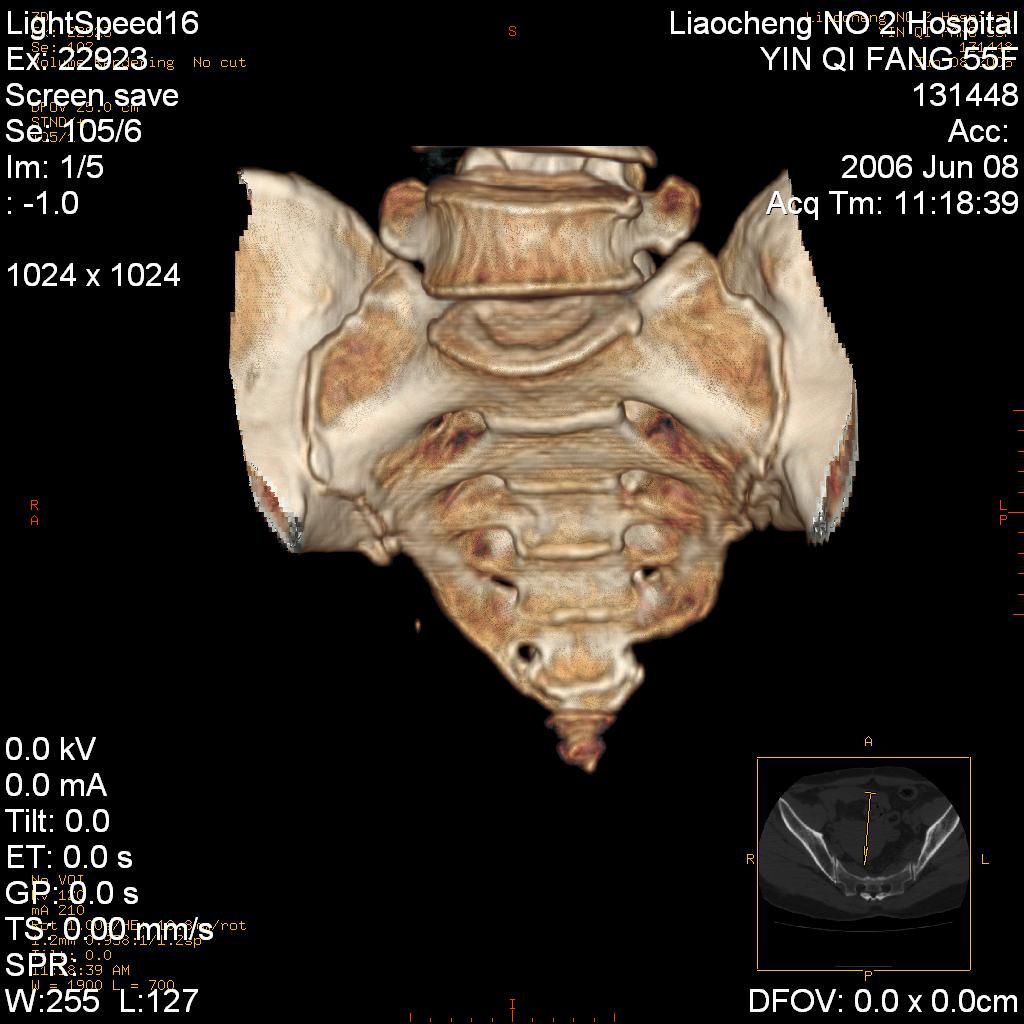

女,55岁,十余年前骶尾骨摔伤,x线平片诊断骶骨裂纹骨折,现在骶尾部又疼痛2月,x线怀疑骶骨左下部骨质破坏。大家看看,是不是先天变异。正常人不是只有4个骶孔吗?怎么此病例有5个?

三维做的不错,好像没什么病。

dg 三维很好,佩服

两侧骶髂关节炎,确实做得很漂亮

众口一词啊,图象确实漂亮,羡煞人也!右侧骶髂关节间隙变窄,相对缘增生硬化,髂骨侧增生明显。左侧轻微类似改变,考虑双侧骶髂关节炎。余未见异常。

考虑双侧骶髂关节炎。余未见异常。

图像确实漂亮,骶髂关节及骶尾椎均未见异常。

支持骶髂关节炎,3d做得很漂亮!!!!

三维作的很漂亮,真羡慕。